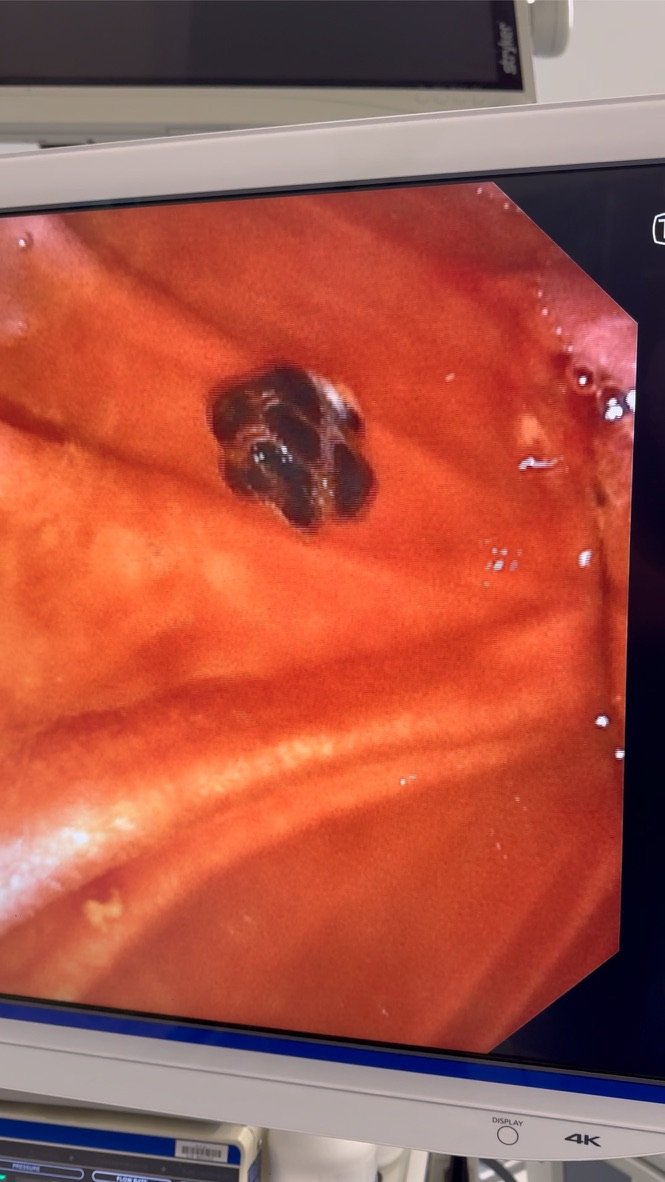

Example images (de-identified, illustrative)

These are examples from a real case. They are included for education only and are not for diagnostic use.

Zoomed image of gallbladder stones on imaging

Close-up: multiple stones (“gravel”) surrounding a larger stone.